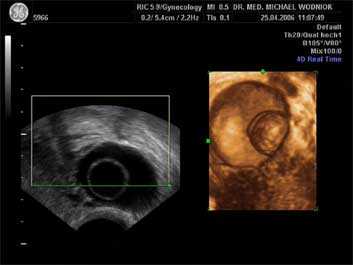

Ultraschall des kleinen Beckens mit der Vaginalsonde Die Ultraschalluntersuchung ist ein bildgebendes Verfahren, welches die Reflektion oder Echos von Ultraschallwellen in den unterschiedlichen Geweben und Organen ausnützt um computergestützt Schnittbilder aus dem Inneren des Körpers zu erstellen. Durch moderne hochleistungsfähige Mikroprozessoren ist es in den letzten Jahren möglich geworden, auch 3-dimensionale oder sogar bewegte 3-dimensionale (4-D) Bilder bzw. Bildsequenzen zu erzeugen. Beides können wir Ihnen in der Praxis anbieten. Eine Ultraschalluntersuchung ist ungefährlich und schmerzfrei. Durch die Anwendung von Dopplerverfahren, mit welchen wir den Blutfluss in den Organen feststellen und messen können, erweitern wir die Untersuchung um die funktionelle Dimension. Ein weiterer Bestandteil unseres Leistungsspektrums ist die farbkodierte Dopplersonographie. Farbkodiert sind entweder die Richtung des Blutflusses oder dessen Intensität. Über die computergestütze Berechnung des Blutflusswiderstandes ist im Einzelnen eine Aussage bzw. Vorhersage über die qualitative und quantitative Durchblutung möglich. (Plazentadurchblutung, kindliche Blutgefässe, Durchblutungsmuster bei verschiedenen Tumoren des Unterleibes und der Brustdrüsen) Ultraschalluntersuchungen haben in unserem Fachgebiet vielfältige Anwendungsmöglichkeiten gefunden. Besonders faszinierend ist der Einsatz im Bereich der vorgeburtlichen Diagnostik. Bereits in der 10. Schwangerschaftswoche ist es möglich, die Extremitäten des Embryos darzustellen und Aussagen zum Körperumrissbild zu machen (Ausschluss von Spaltbildungen, Nackentransparenzmessung). Auch im Bereich der Gynäkologie ist die Bedeutung des Ultraschalls stetig gewachsen und hat sich als erweiterte Vorsorge etabliert. Durch die vaginale Ultraschalluntersuchung können bereits kleine Veränderungen entdeckt werden, die sich der manuellen Tastuntersuchung noch entziehen. Auffällige Tastbefunde an den Eierstöcken sind durch den Einsatz von 3D / 4D in Kombination mit der Farbdoppleruntersuchung besser interpretierbar und können dadurch Frauen unnötige abklärende Operation ersparen. Die Anwendung des 3D Ultraschall, insbesondere im Coronarschnitt, lässt eine effektive Beurteilung für Veränderungen (Polypen, Karzinome) der Gebärmutterschleimhaut zu. ![]() ![]() ![]() ![]() ![]() |